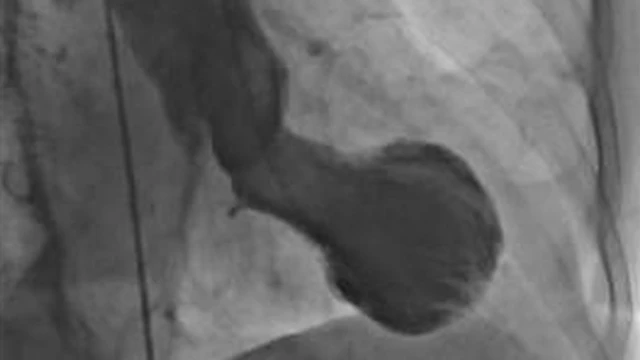

این سندرم به نام "سندرم تاکوتسوبو" هم شناخته میشود. دلیل این نامگذاری، شکل قلب افراد دارای این شرایط است که به کوزهای ژاپنی به همین نام شباهت دارد. دلیل سندرم قلب شکسته میتواند شوکه شدن فرد باشد.

منبع تصویر، Christian Templin, University Hospital Zurich